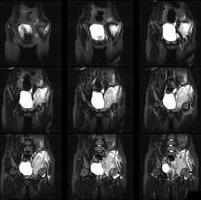

女, 16 岁, 左髂部疼痛,软组织肿块

女, 16 岁, 左髂部疼痛,软组织肿块数月,髋关节活动受限。 左髂骨溶骨性破坏,伴有巨大软组织肿块,病灶累及髋臼。考虑骨肉瘤可能大。...